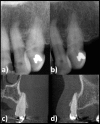

Objectives: The aim was to assess to what extent cone beam CT (CBCT) used in accordance with current European Commission guidelines in a normal clinical setting has an impact on therapeutic decisions in a population referred for endodontic problems.

Methods: The study includes data of consecutively examined patients collected from October 2011 to December 2012. From 2 different endodontic specialist clinics, 57 patients were referred for a CBCT examination using criteria in accordance with current European guidelines. The CBCT examinations were performed using similar equipment and standardized among clinics. After a thorough clinical examination, but before CBCT, the examiner made a preliminary therapy plan which was recorded. After the CBCT examination, the same examiner made a new therapy plan. Therapy plans both before and after the CBCT examination were plotted for 53 patients and 81 teeth. As four patients had incomplete protocols, they were not included in the final analysis.

Results: 4% of the patients referred to endodontic clinics during the study period were examined with CBCT. The most frequent reason for referral to CBCT examination was to differentiate pathology from normal anatomy, this was the case in 24 patients (45% of the cases). The primary outcome was therapy plan changes that could be attributed to CBCT examination. There were changes in 28 patients (53%).

Conclusions: CBCT has a significant impact on therapeutic decision efficacy in endodontics when used in concordance with the current European Commission guidelines.